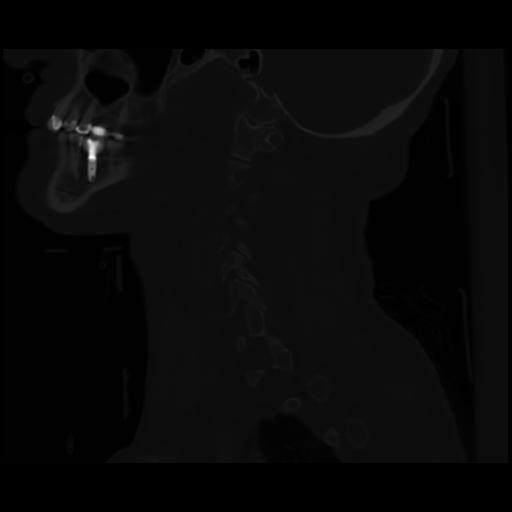

14 P.BLANDAS,,Sagittal,2.000,P.BLANDAS,Sagittal,